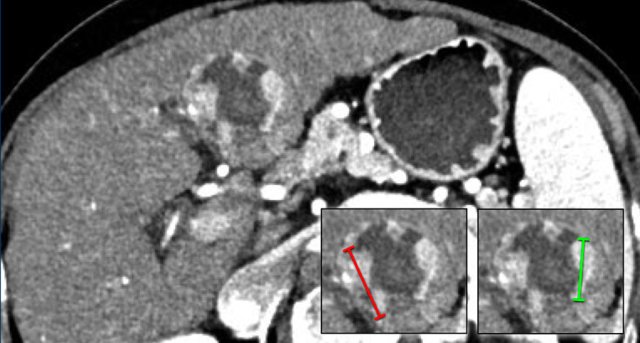

The images show an only mild rim-like arterially enhancing lesion in segment V with washout.

A linear area of hypoenhancement is seen extending from the mass which is suspicious of tumor in vein (yellow arrow).

Since we are not absolutely sure that it is a tumor thrombus, we cannot categorize this as LR-TIV.

A follow up CT was done, showing severe progression of the tumor as well as vascular involvement of the anterior right portal vein (white arrow).

Now we are sure of tumor invasion in the portal vein.